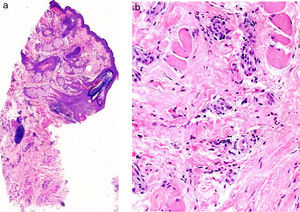

Mujer de 37 años sin antecedentes personales de interés que acude a la consulta de dermatología por una lesión en el mentón de varios meses de evolución, asintomática. A la exploración presentaba un nódulo marronáceo, de 2cm de diámetro, de consistencia elástica (fig. 1). La paciente no presentaba adenopatías palpables. Se realizó la extirpación quirúrgica de la lesión. En el estudio histológico se evidenció una epidermis sin alteraciones, con presencia en las capas profundas de vasos recubiertos por células endoteliales de aspecto epitelioide, agregados linfocitarios y eosinófilos (fig. 2 A y B). En la analítica se detectó eosinofilia, sin alteraciones en el resto de las determinaciones de laboratorio. Con los hallazgos obtenidos se realizó el diagnóstico de HALE. Durante toda la evolución se ha realizado seguimiento ecográfico (Esaote My Lab One, sonda líneal de frecuencia variable 18-22MHz, resolución lateral 240micras), objetivándose una masa de bordes mal delimitados en la dermis, compuesta por haces hiperecoicos e hipoecoicos entrelazados, formando una imagen en «ovillo de lana» (fig. 3 A), rodeada por un halo hiperecoico. En el estudio doppler (Esaote My Lab One, sonda líneal, modo power doppler, frecuencia 18MHz, PRF 750MHz) se evidenció un aumento de vascularización (fig. 3 B). Esta imagen se ha mantenido sin cambios a pesar de los tratamientos realizados.